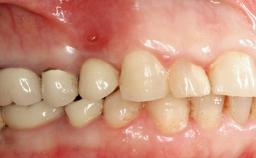

A 65-year-old female patient was referred to the periodontist for assessment and management of implant site 12. Implant 12 had been placed ten years previously and restored with a cemented single crown. The patient was a non-smoker in good general and periodontal health. On examination there were 7 mm probing depths at implant 12 with suppuration and bleeding on probing. The patient was aware of the presence of pus but had no discomfort. A periapical radiograph showed marginal bone loss to approximately the third thread of the implant. Previous radiographs obtained from the referring clinician indicated that there had been progressive bone loss since the implant was restored. A diagnosis of periimplantitis was made.